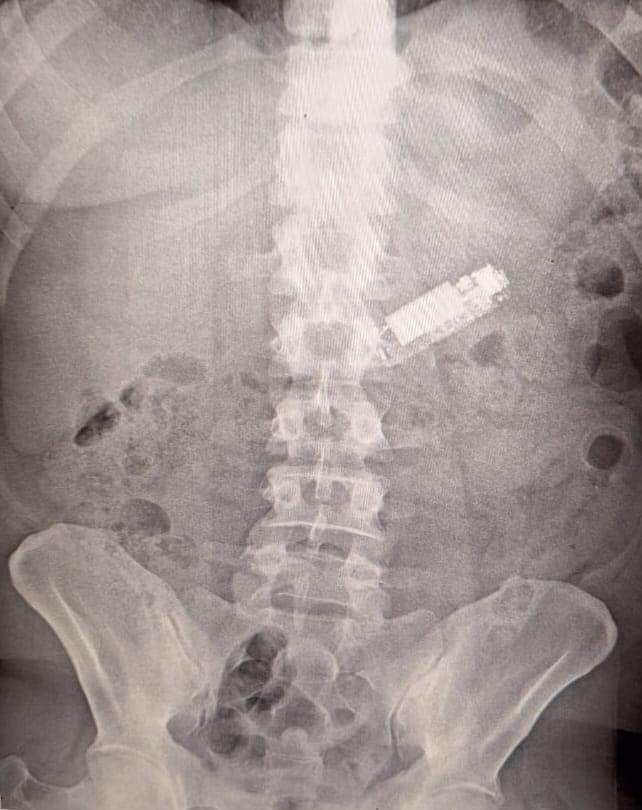

واستقبلت وحدة الطوارئ بمستشفيات جامعـة طنطـا مريض فى العقد الرابع من العمر يعانى من وجود "هاتف محمول” ابتلعه بطريق الخطأ لمدة 5 شهور داخل البطن وتم إجراء كافة الفحوصات الطبية ومنها أشعة عادية على البطن لتحديد مكان الهاتف المحمول وأشارت الأشعة إلى وجوده داخل المعدة وتم إجراء منظار على البطن استمر لمدة ساعة وتم إخراجه من بطن المريض الذى غادر المستشفى بعد استقرار حالته الصحية.